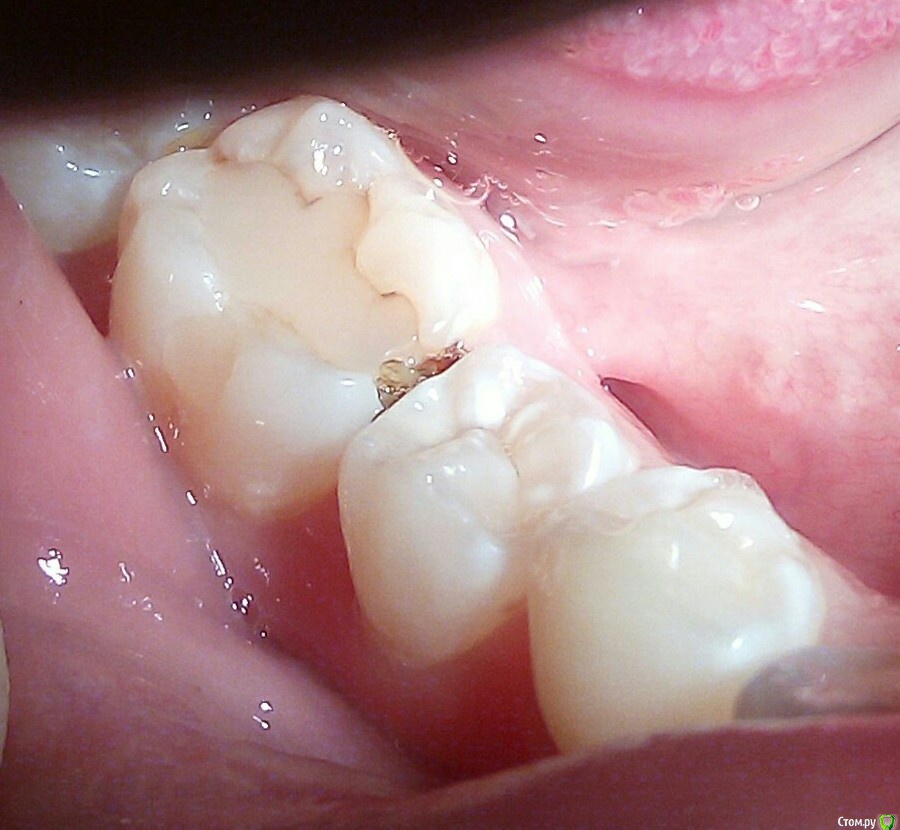

igorstom Опубликовано 24 ноября, 2019 Автор Поделиться Опубликовано 24 ноября, 2019 Ещё один пример кариеса корня зуба 3.7. Но в данном случае он неглубокий. Понятно, что световые пломбы к цементу корня не фиксируются, и 100% будет нарушение краевого прилегания, и отсюда вторичный кариес. Вопрос. Как же выйти из ситуации в данном случае, если световые пломбы в месте прилегания к корню не фиксирутся? Потом расскажу, как делаю я. Но хотелось бы услышать другие мнения. Может у кого-то есть идеи получше, чем мои решения..И да, сразу пример по поводу перелечивания каналов. Я берусь за перелечку чужого эндо, но только платно. 1 Ссылка на комментарий